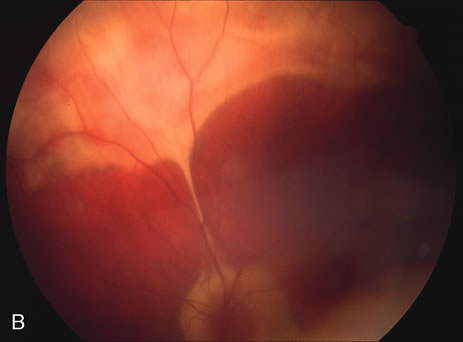

Some patients present with subretinal bands that extend between chorioretinal scars. In addition there may be initial active yellow choroidal lesions that subsequently become atrophic. Vitreous cells are usually present although they may be few and difficult to detect. Visual acuity loss in these cases may be due to active choroidal neovascularization, subretinal bands under the fovea, or from cystoid macular edema. The vast majority of affected patients are women with a mean age of 27 years and both eyes are usually involved. The affected individuals tend to be myopic.49 The age range is from 6 years to 76 years and there is no racial predilection.40 Whether it is a separate disease or a more severe form of multifocal choroiditis is controversial (Figs. 10 and 11). Aggressive therapy is warranted because it has a poorer prognosis than most cases of multifocal choroiditis. This syndrome has been called either diffuse subretinal fibrosis or progressive subretinal fibrosis syndrome.

Fig. 10. A. Fundus photograph showing the subretinal fibrosis extending from the disc to the periphery in a case of diffuse subretinal fibrosis. B. Fundus photograph showing the marked fibrosis in the midperiphery. C. Multifocal choroiditis type lesions noted in the inferior retina.